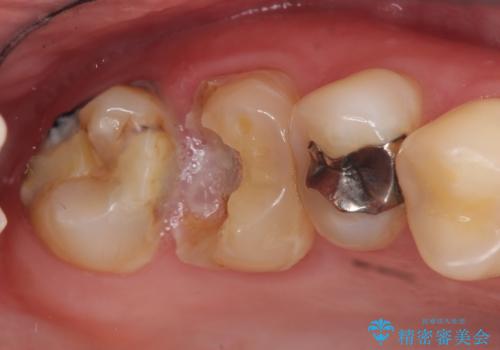

セラミックインレーによる虫歯治療

- 矯正治療希望で来院され、左上5に大きな虫歯があった患者様の症例です。虫歯除去後、矯正中はプラスチックによる仮詰めを行い、矯正終了後プラスチックを除去し、セラミックインレーで再補綴しました。

セラミックインレーによる修復

当院のセラミックインレーはemaxという強度と審美性に優れた材料を使用しています。

またプレス方式でインレーを製作しているため、削り出しで製作するCADCAMより優れた適合性も持ち合わせており、二次的な虫歯になりにくい修復物です。